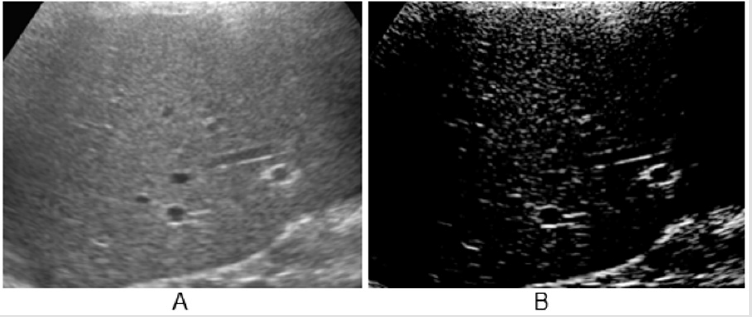

Figure 2: A: Aspect of HR scan, lung ‘slice’ (Preirus, Hitachi).

B: High-density white components in normal lung (<8% of the total image).

Lung Ultrasound: a section of lung is imaged (Figure 1) in a vertical scan. The image is elaborated (Adobe Premiere) for white components (speckles), corresponding to the most fibrotic components and areas of fibrosis in a normalized grey scale. The grey scale median is an expression of the white components (fibrotic, associated with collagen) in the ultrasound section. The section is obtained with a vertical, trans axillary scan (arm elevated). The ‘slices’ [4] are scanned for fibrotic components and for vascularization. The content of white ‘speckles’ corresponds to the presence of fibrotic elements. In a normal lung section of this type, the white components are about 8% of the section or less. Figure 2 shows an elaboration of a ‘slice’ of lung tissue with its ‘white’ components corresponding to high collagen level (full black is the density of blood). The same software is used to image the arterial plaques to define their content in fibrotic (white) components or i.e., thrombotic (black on ultrasound scans, same density of blood). Supplement study: This study (and the subsequent post-COVID-19 lung study) were conducted as supplement registry studies [8,9]. The role of the combination Pycnogenol®-Centellicum® to control fibrosis has been previously defined in several clinical models [10]. 150 mg/day of Pycnogenol® was administered in 3 doses and Centellicum® (centella asiatica) was given at the doses of 225 mg 3 times per day. Both supplements are produced by Horphag Research.